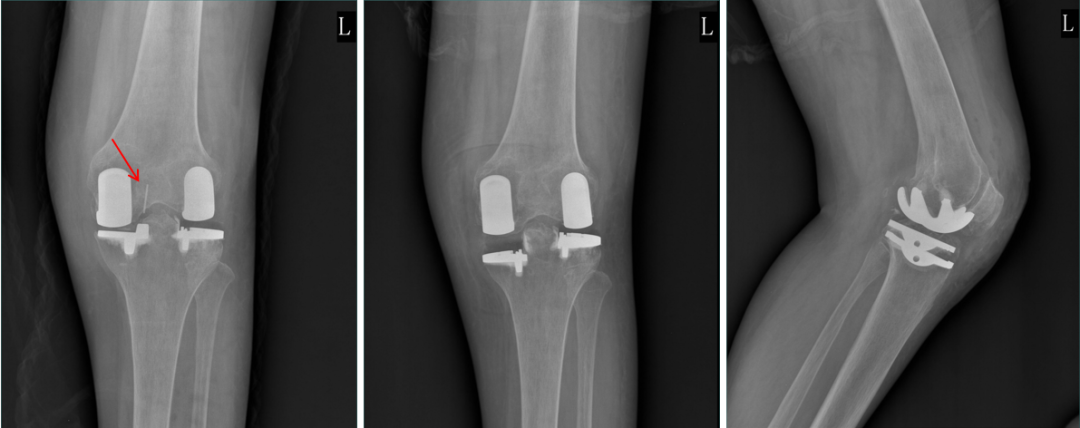

正位片标准胫骨和股骨假体位置

AP位假体位置:胫骨假体无明显内外翻,与胫骨轴线垂直,内侧缘与胫骨平台内侧缘齐平; 股骨假体长轴与胫骨假体垂直,中线一致。

胫骨假体3°内翻

AP位胫骨与股骨假体位置:胫骨假体内翻3°,股骨假体中轴线与胫骨假体垂直。

胫骨假体内侧悬挂

AP位胫骨假体位置:胫骨假体内侧悬挂>2mm。

股骨假体偏内放置

AP位胫骨与股骨假体位置:股骨假体轻度内翻,中轴线与胫骨假体中线不一致,偏内侧。